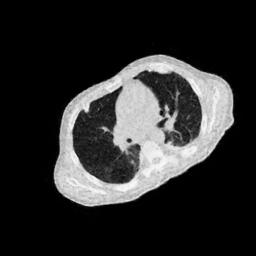

IV-F Real CT Reconstruction

To further verify the effectiveness of the RBP-DIP framework, real CT data from the Finnish Inverse Problem Society [49, 50] was used to validate our algorithm. The few-view and limited-angle reconstruction results are shown in Figure 12. Due to the lack of available training sets, pre-trained models were not included in the experiments. Different from the previous experiment, data from Finnish Inverse Problem Society is highly noisy. However, it is still evident that the RBP-DIP outperforms all other algorithms in all experiments, even under high noise and highly ill-posed conditions.

(a) Reference

8.41dB/0.34

(b) ASD-POCS

12.77dB/0.31

(c) DIP

14.59dB/0.45

(d) RBP-DIP